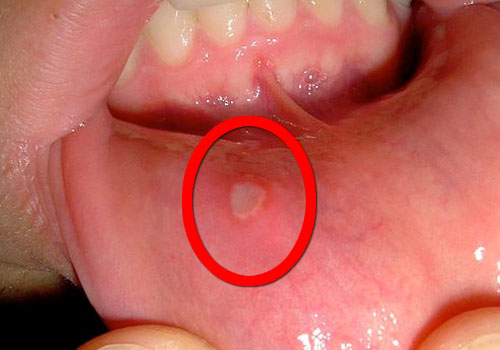

Para falar sobre este assunto, precisamos saber que as aftas bucais são um tipo de úlcera ou chaga bucal que provoca muita dor.

De cor branca ou amarela, são rodeadas por uma área de cor vermelha brilhante e estão associadas às infecções virais, mas em alguns casos não se diagnostica exatamente sua causa.

- Mancha vermelha e dolorosa que se transforma em uma úlcera aberta.

- Úlcera de cor amarela.

A dor provocada pelas aftas normalmente dura entre 7 e 10 dias. Pode se estender por até aproximadamente 3 semanas, dependendo de sua gravidade.